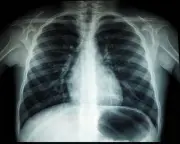

Jabatan Kesihatan Kelantan sedang menyiasat kematian mengejut seorang doktor pelatih berusia 29 tahun di Hospital Sultan Ismail Petra, Kuala Krai. Siasatan menyeluruh termasuk faktor tekanan kerja sedang dijalankan.